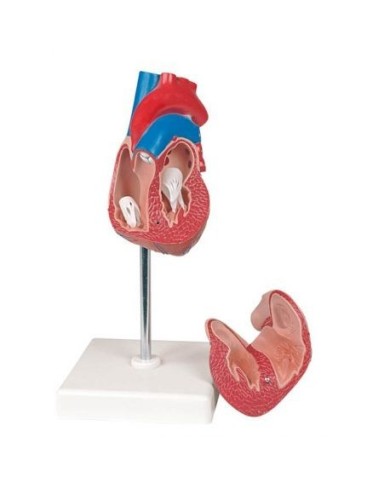

Fra i modelli di base segnaliamo il modello di cuore classico in due parti, in cui le due metà del cuore sono tenute insieme da potenti magneti.

Inoltre nella categoria sono presenti anche i modellini anatomici di cuore con bypass e con sistema di conduzione, fino ai modelli anatomici comparativi di patologie del cuore.